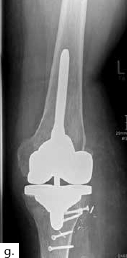

Sechs Monate später konnte bei solide eingeheiltem Knochenblock (Abb. 2f) eine teilgekoppelte Kniegelenkprothese implantiert werden, deren Bedeckung in der Folge durch die ausreichend dimensionierten Lappenplastiken unproblematisch war (Abb. 2g u. h). Der Patient erzielte nach Rehabilitationsmaßnahmen eine vollständige Belastungsfähigkeit bei freier Kniegelenkbeweglichkeit und solide verheiltem Integument (Abb. 2i u. j).